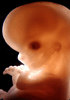

Carnegie Stage 23 (56 post-ovulatory days)

Most embryos at stage 23 are approximately 56-57 postovulatory days old and measure 23-32 mm in length. Distinguishing criteria for this stage include fusion of the eyelids at the medial and lateral margins, clear distinction of the subdivisions of the upper and lower limbs, the forearms appear at or above the level of the shoulders, the superficial vascular plexus of the head is very close to the vertex, and the external genitalia are well developed but not always sufficiently to distinguish the embryo's sex.

(NOTE: These specimens are late stage 23.)